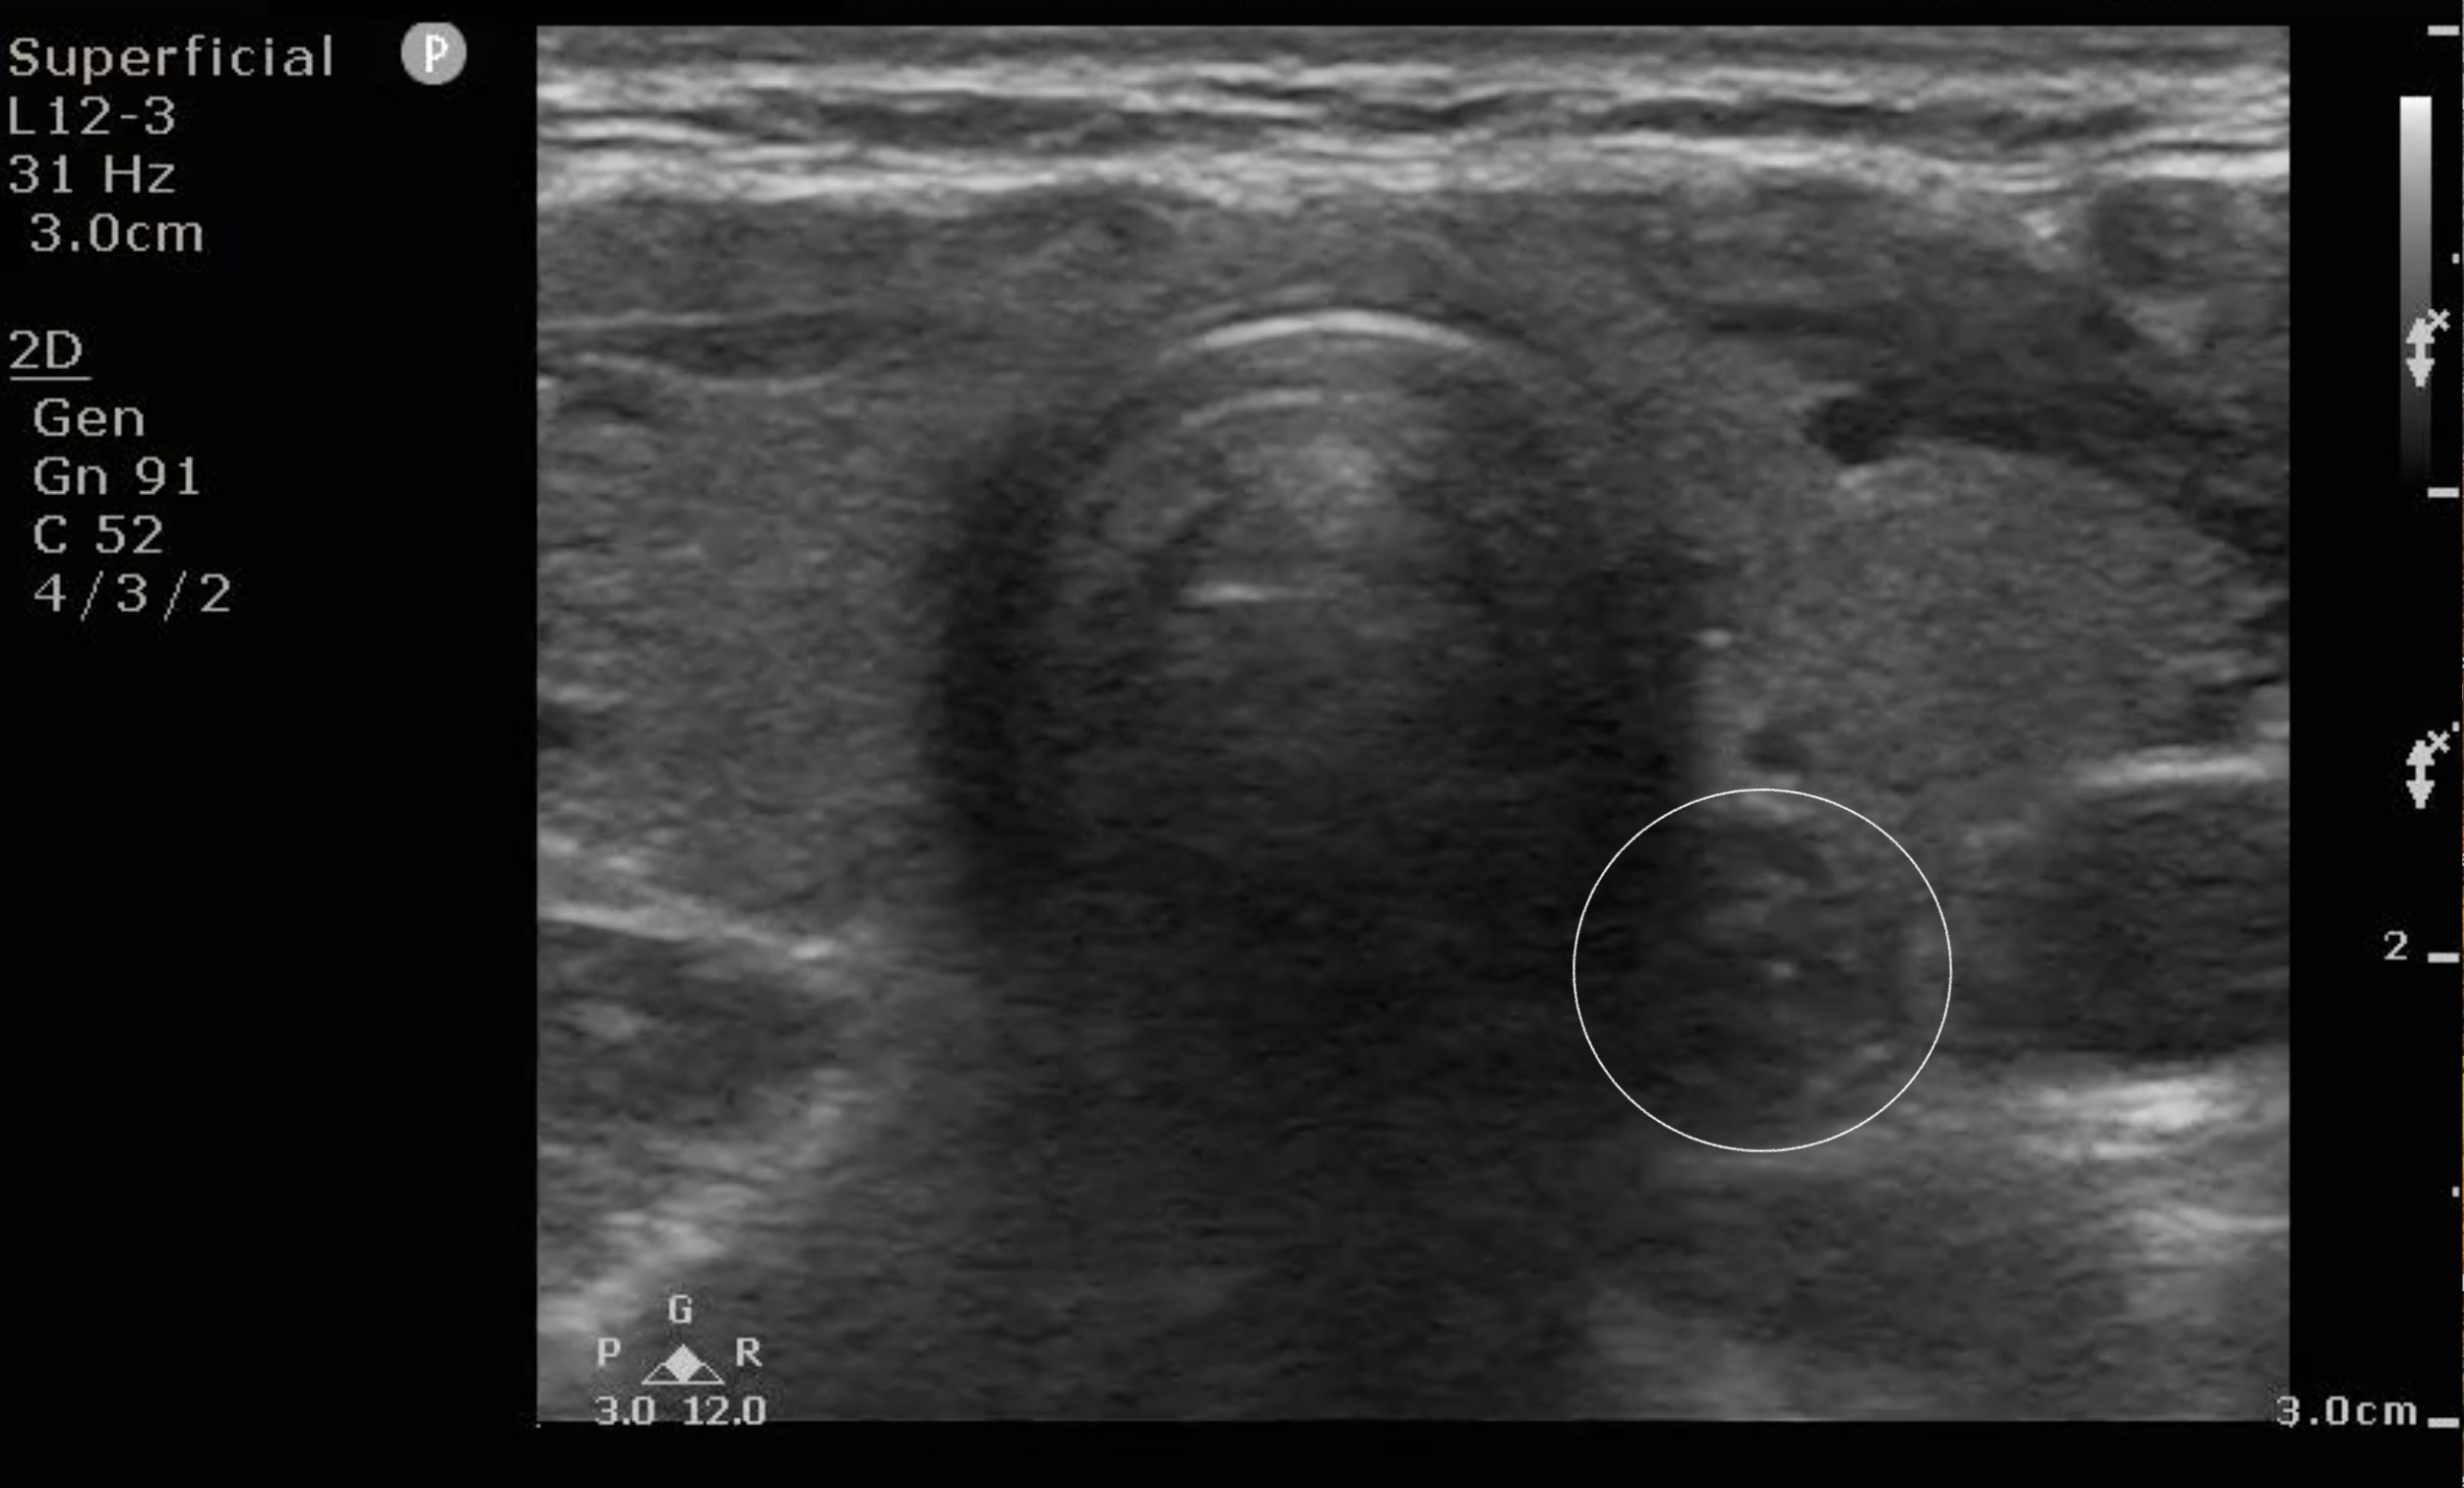

- Figure 7a and b. Step 7: Just caudal to the cricoid cartilage, you will start to see trachea with its intermittent tracheal rings. To the left of the patient’s trachea, you will frequently see the esophagus with a bull’s eye appearance (circle).

- Video 2. You can also have the patient swallow, and you will see air move through the esophagus in real time.